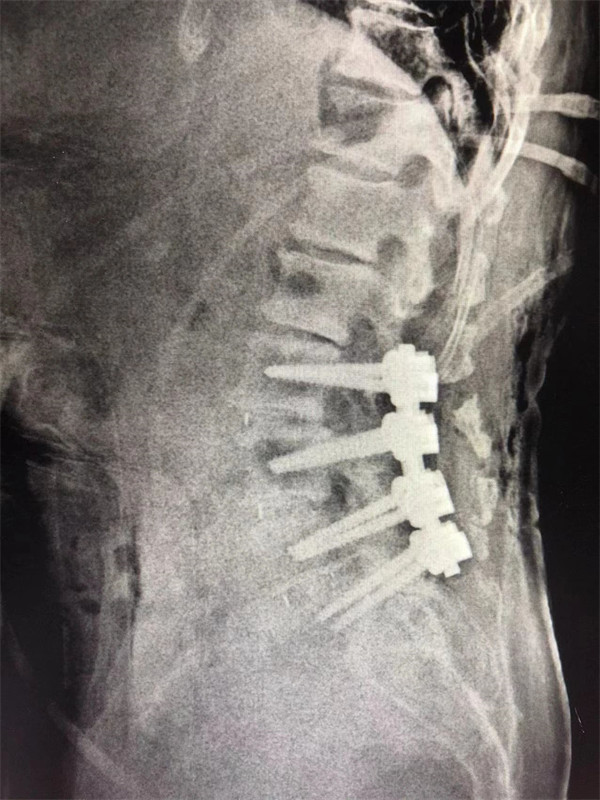

戈才華主任團隊討論病情及手術風險,并與麻醉科醫(yī)生多次討論術中麻醉風險,經過詳盡周密的布置之后,最終給阿婆在全麻下進行腰3/4,4/5,腰5/骶1腰椎椎體間融合術。

手術后↓